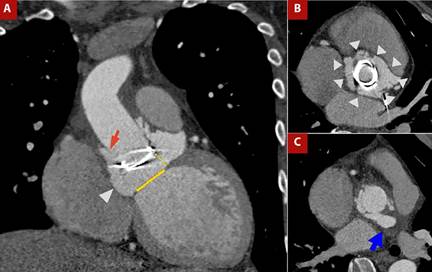

Figure 4 shows the case of a patient with prosthetic valve infective endocarditis, in whom CT demonstrated prosthetic valve migration, vascular graft dehiscence with paravalvular leak, and a retroaortic paravalvular abscess.

Figure 4 A) Contrast-enhanced CT angiography of the thoracic aorta with cardiac gating, coronal view. B) Orthogonal plane at the aortic root and C) Ascending aorta. Patient with Marfan syndrome, prior aortic valve prosthesis, and Bentall procedure, now presenting with prosthetic valve endocarditis. Findings include migration of the prosthetic valve (yellow dashed line in A) from the aortic valve plane (yellow solid line in A), dehiscence of the vascular graft (red arrow in A), circumferential (360°) paravalvular leak surrounding the prosthesis (arrowheads in A and B), and a retroaortic paravalvular abscess (blue arrow in C).